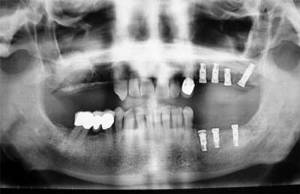

f20f20Implantes dentales, inclusiones dentarias (caninos incluidos y cordales o muelas del juicio), quistes y tumoraciones de los maxilares, boca, cabeza y cuello, cirugía de los tejidos blandos de la boca (làser de CO2), patología y cirugía de las encías (periodoncia), cáncer de la boca, deformidades dentofaciales, traumatismos de la boca y de la cara, patología de las glándulas salivares.